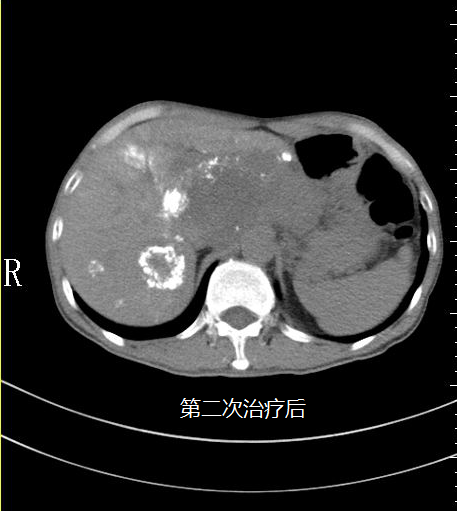

苏先生进行第二次微血管介入治疗后明显感受自己的身体变得轻盈,可以进行简单的饮食,精神状态变好了。

在5月3日苏先生的肝指标检查中甲胎蛋白降为6671IU/ml(参考值0~5.8),随后王峰医生实时跟进苏先生病情为他制定后续的治疗方案,为他开对应的药物治疗;5月14日苏先生的肝指标检查中甲胎蛋白降为18.70U/ml(参考值0~5.8)。

5月18日是苏先生进行第三次微血管介入治疗,治疗后苏先生完全可以自理,饮食恢复正常,面色也慢慢红润起来,肿瘤从原来的16公分缩小至10公分,甲胎蛋白逐渐趋向正常,看到这样的结果也让医生们深感很欣慰,连苏先生也意想不到,前段时间自己还是生命濒危的癌症患者现在却可以像正常人一样生活。他觉得这是上天给他最大的惊喜。